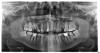

Доброго времени суток. Прикладываю панорманый снимок челюсти. 16 и 25 зубы сильно разрушены, врач в клинике, в которую я обратился говорит, что их обязательно нужно удалять. Неужели нельзя никак наростить? Большая просьба - посмотрите, пожалуйста - действительно ли ничего невозможно? И если не сложно какие еще проблемные места. Их полно на самом деле. Заранее спасибо

16 и 25 - действительно удалять, они сильно разрушены, также удалять 37 - киста на корнях + зуб разрушен, также удалять 48, он упирается в 47, в этом месте на 47 кариес, чтоб его пролечить нужно убрать 48, иначе может развиться пульпит бессимптомно. Также все 8 зубы удалять.

Лечения требуют 15, 13, 12, 22, 24, 26 (возможно пульпит).

46, 36 - перелечить каналы и под коронки. 11 зуб - убрать штифт, перелечить канал и тоже под коронку.

Также нужна консультация ортодонта - у Вас 15 съехал на место 14, тесно стоят передние нижние зубы ( и передние верхние?)

После лечения и удаления - рациональное протезирование имплантатами.